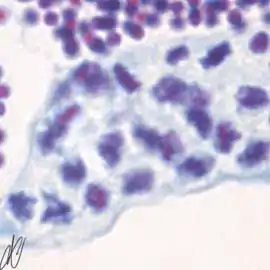

spermatogenesiscysts with successive stages of spermatogenesis in a seminiferous tubule | |||

| H&E | Putt's carbol fuchsin as a marker of spermatogenic maturation |